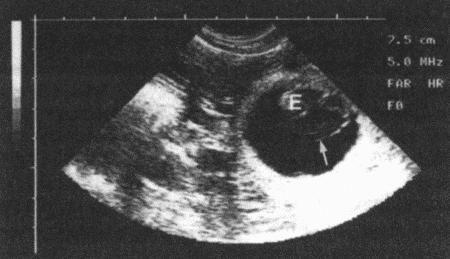

Фиг. 11.4.

Ультразвуковое изображение единственного плодного яйца, видны эмбрион (Е), плодные оболочки (стрелка) и окружающая их анэхогенная жидкость в аллантоисе. Датчик на 5МГц, шкала в см